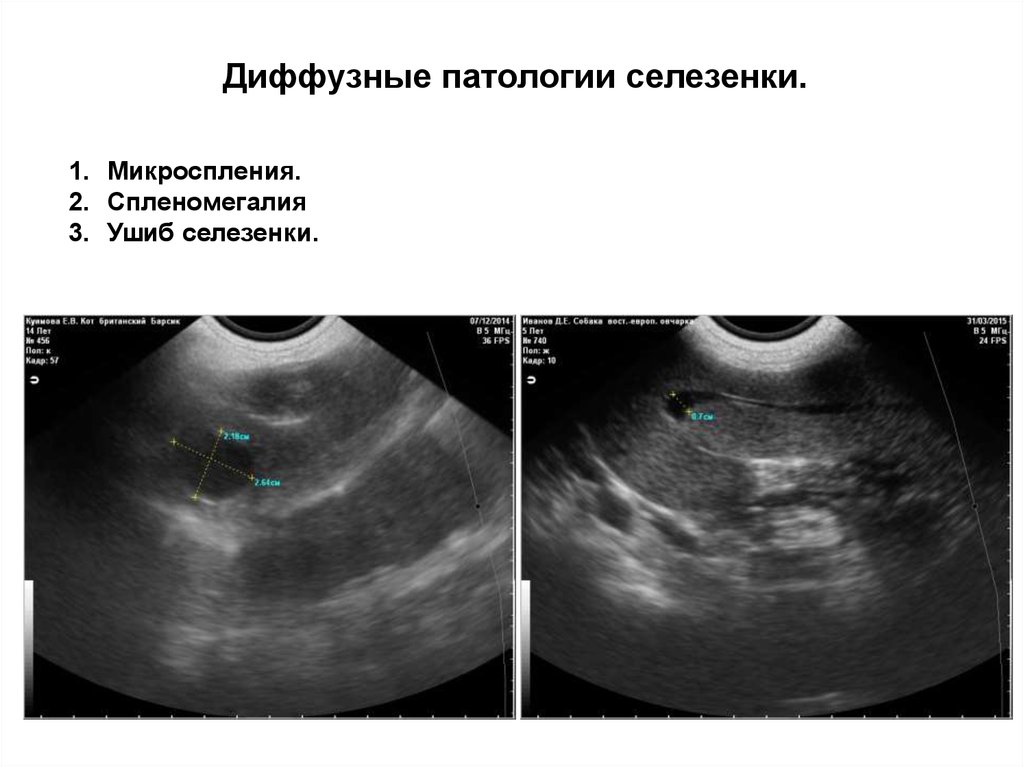

Диффузные патологии селезенки.

1. Микроспления.

2. Спленомегалия

3. Ушиб селезенки.